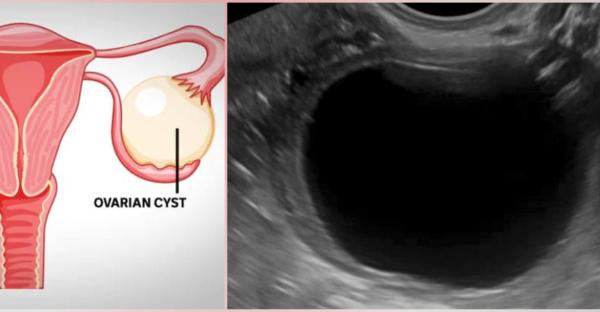

What is Ovarian Cyst ??